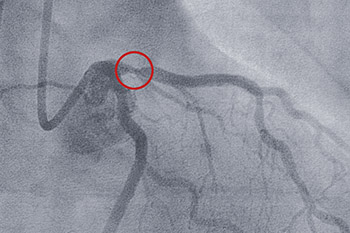

With compassion and respect, our heart and vascular experts deliver innovative procedures and treatments using advanced technology and years of experience. Our goal? To help you heal and become healthier.